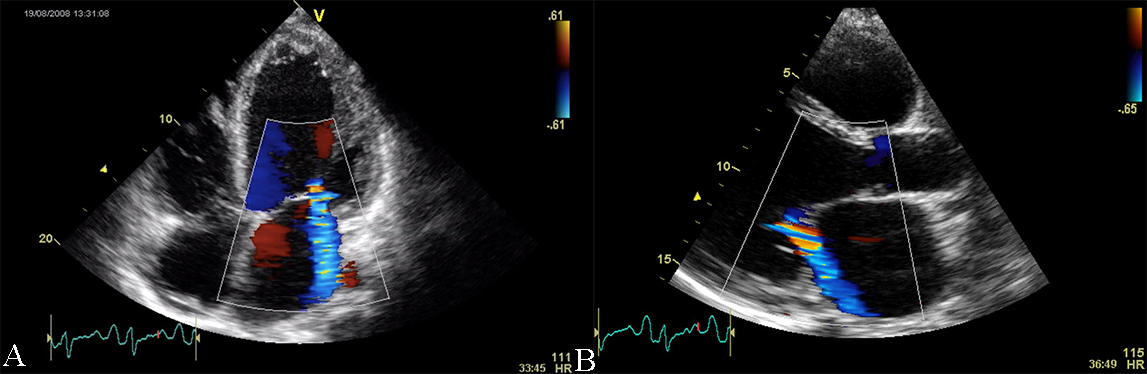

Color and spectral Doppler echocardiography is of limited use in the diagnosis

of DCM, except for atrioventricular valve incompetence. One constant feature is

the presence of mitral regurgitation, secondary to the annulus dilation with

abnormal leaflet tethering. Mitral regurgitation can present with different

degrees of severity and is an additional prognostic factor (see Fig. 3 and

Appendix Video 2 and 3). The pathophysiology of mitral regurgitation in DCM is usually

due to abnormal leaflet tethering mandated by the change in LV shape from

ellipsoid to spherical. As cardiomyopathy progresses, the point of leaflet

coaptation migrates from its normal basal location to a spot deeper in the LV

cavity this leading to also to an apposition defect with the generation of an

eccentric regurgitant jet. Moreover, DCM patients present with an abnormally low

diastolic function [5]. Restrictive or pseudo-normal diastolic inflow patterns

impact the patients with DCM, with an associated poor prognosis [10, 11]. The

assessment of the pulmonary vein flow signal as an adjunct to the mitral inflow

pattern is very important in the echographic evaluation of DCM. Abnormal

pulmonary venous systolic flow patterns have been shown to correlate with the

future development of pulmonary hypertension. Loss of the systolic dominant flow

pattern suggests elevated filling pressure and the difference between the

pulmonary venous flow reversal duration and the mitral inflow duration during

atrial contraction greater than 30 ms predicts mortality and hospitalization [9].

Studies evaluating diastolic compliance with Doppler echocardiography have shown

also an altered mitral diastolic flow with a short deceleration time

Fig. 3.Echocardiographic aspect of DCM in a patient with idiopathic dilated cardiomyopathy. (A) Apical 4 chamber view, showing dilated left ventricle, dilated left atrium, and significant secondary mitral regurgitation flow with Coanda effect. (B) Parasternal long-axis view, showing dilated left ventricle, dilated left atrium, and significant secondary mitral regurgitation flow with Coanda effect. An online video of this patient with idiopathic dilated cardiomyopathy is available (Appendix Video 2 and 3).